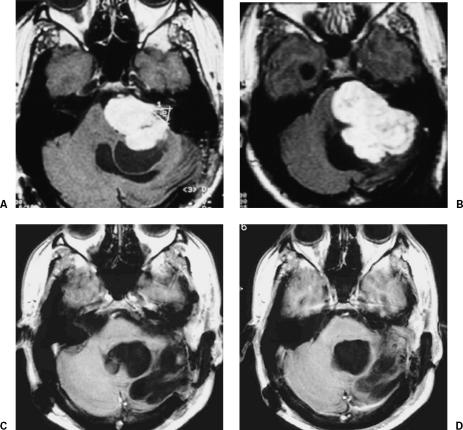

术前情况:入院时,患者表现为左侧耳聋,面神经完全麻痹,九和十脑神经麻痹,左侧乳突后区膨出。MRI显示较大的囊性残留或复发性听神经瘤(图1中A、B)。

术后情况:经乙状窦后经鼻道入路将肿瘤完全切除,患者未出现其他缺损。肿瘤切除后2周行舌下/面部吻合术。术后2天出ICU,术后两周出院。手术6个月后,他能够重返工作岗位。术后9年,MRI显示病灶未复发(图1中C、D)。

图1:(A,B)术前钆磁共振成像显示左侧较大的囊性残留或复发性听神经瘤压迫脑干及前区。(C,D)全切除9年后MRI加钆。